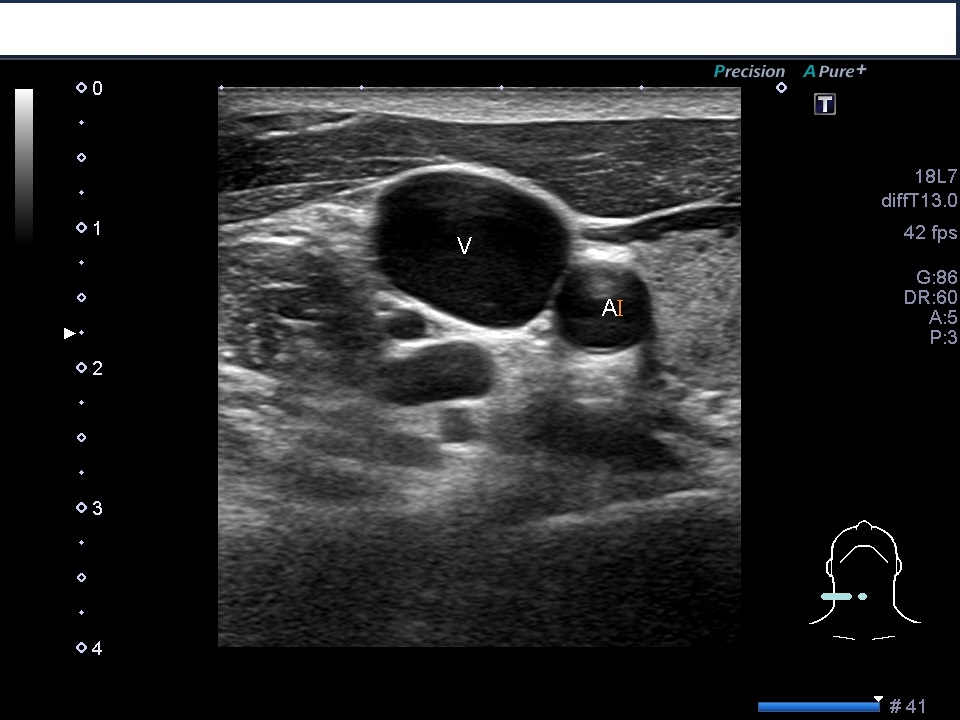

頸部の右内頸静脈と総頚動脈のエコー画像にです。血管はエコーでは黒く映ります。

内側に動脈や甲状腺がみえます。画像を見れば内側に針が向かっていく危険性がわかりますね。

右はプローブを押さえた時の画像です。浅い位置にある静脈は少しの圧排で変形します。ドプラ画像が使えないときは圧排することによって静脈を確認できます。

血管の位置と周りの組織の位置を確認してから、麻酔、穿刺になります。